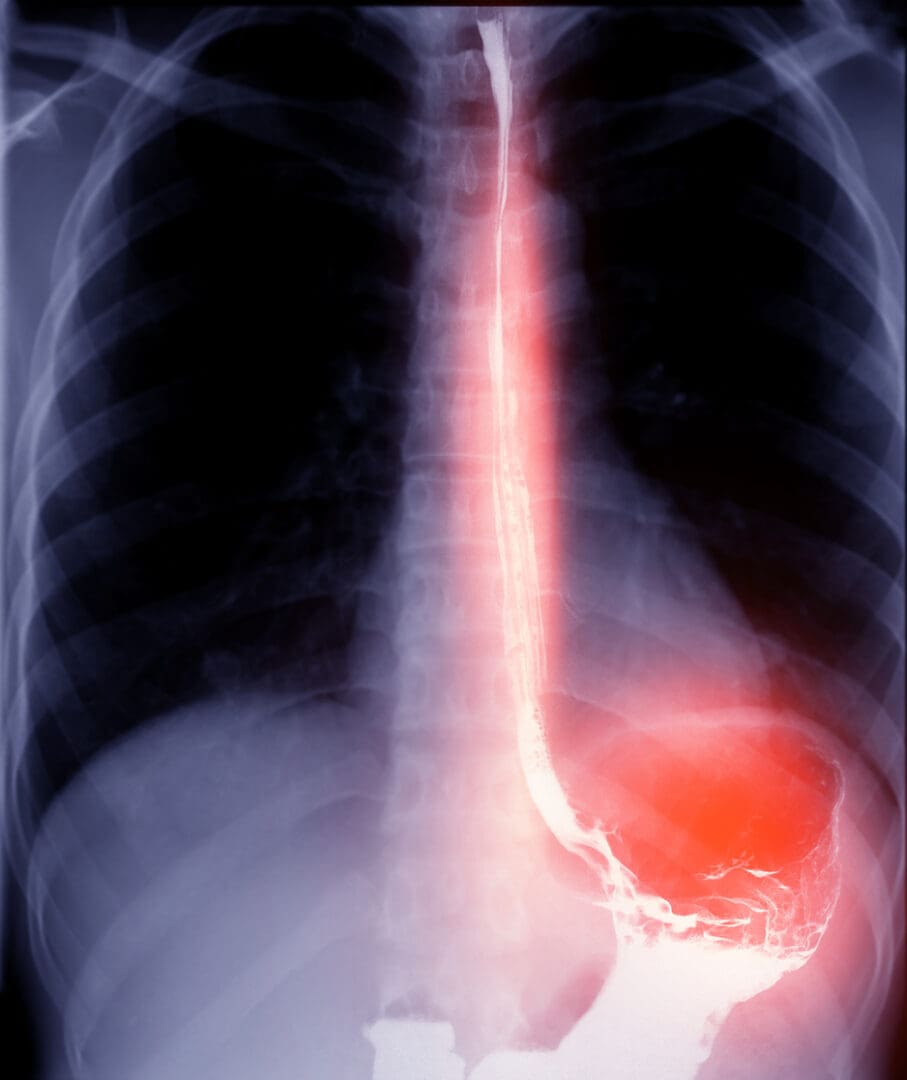

Barium Swallow / Videofluoroscopy

A cup of milky liquid contrast is swallowed and X-ray video is taken.